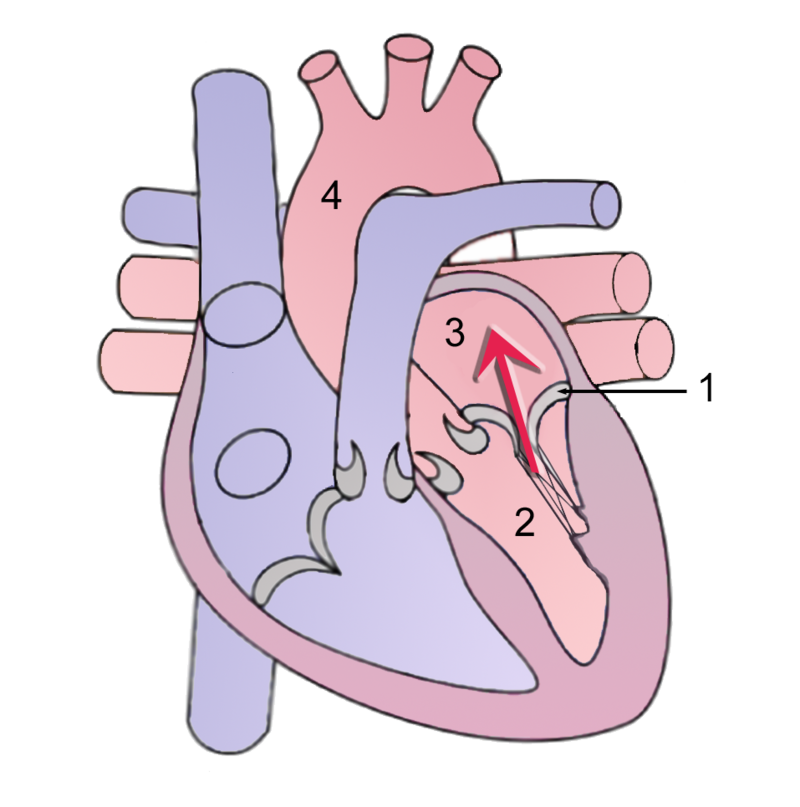

Mitral valve prolapse is the ballooning of the mitral valve into the left atrium during systole.

Mitral valve prolapse is present in 2 – 3% of American adults due to myxoid degeneration of the mitral valve, which causes it to become floppy.

The cause of mitral valve prolapse is unknown, but is associated with myxoid degeneration.

Mitral valve prolapse is associated with two syndromes:

- Marfan syndrome

- Ehlers-Danlos syndrome

Mitral valve prolapse presents with an incidental mid-systolic click followed by a regurgitation murmur that is usually asymptomatic.

Squatting increases the click and murmur volume of mitral valve prolapse due to increased systemic resistance and slows left ventricular emptying.

Complications of mitral valve prolapse include:

- Infectious endocarditis

- Arrhythmia

- Severe mitral valve regurgitation

Treatment of aortic regurgitation is valve replacement.